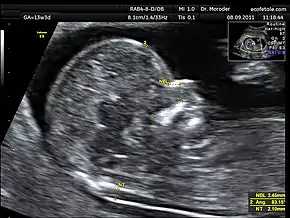

![]() Measurements of fetal nuchal translucency, nasal bone and facial angle according to the standards of the Fetal Medicine Foundation | |

A nuchal scan or nuchal translucency (NT) scan/procedure is a sonographic prenatal screening scan (ultrasound) to detect chromosomal abnormalities in a fetus, though altered extracellular matrix composition and limited lymphatic drainage can also be detected.[1]

Nuchal scan (NT procedure) is performed between 11 and 14 weeks of gestation, because the accuracy is best in this period. The scan is obtained with the fetus in sagittal section and a neutral position of the fetal head (neither hyperflexed nor extended, either of which can influence the nuchal translucency thickness). The fetal image is enlarged to fill 75% of the screen, and the maximum thickness is measured, from leading edge to leading edge. It is important to distinguish the nuchal lucency from the underlying amniotic membrane.[8]